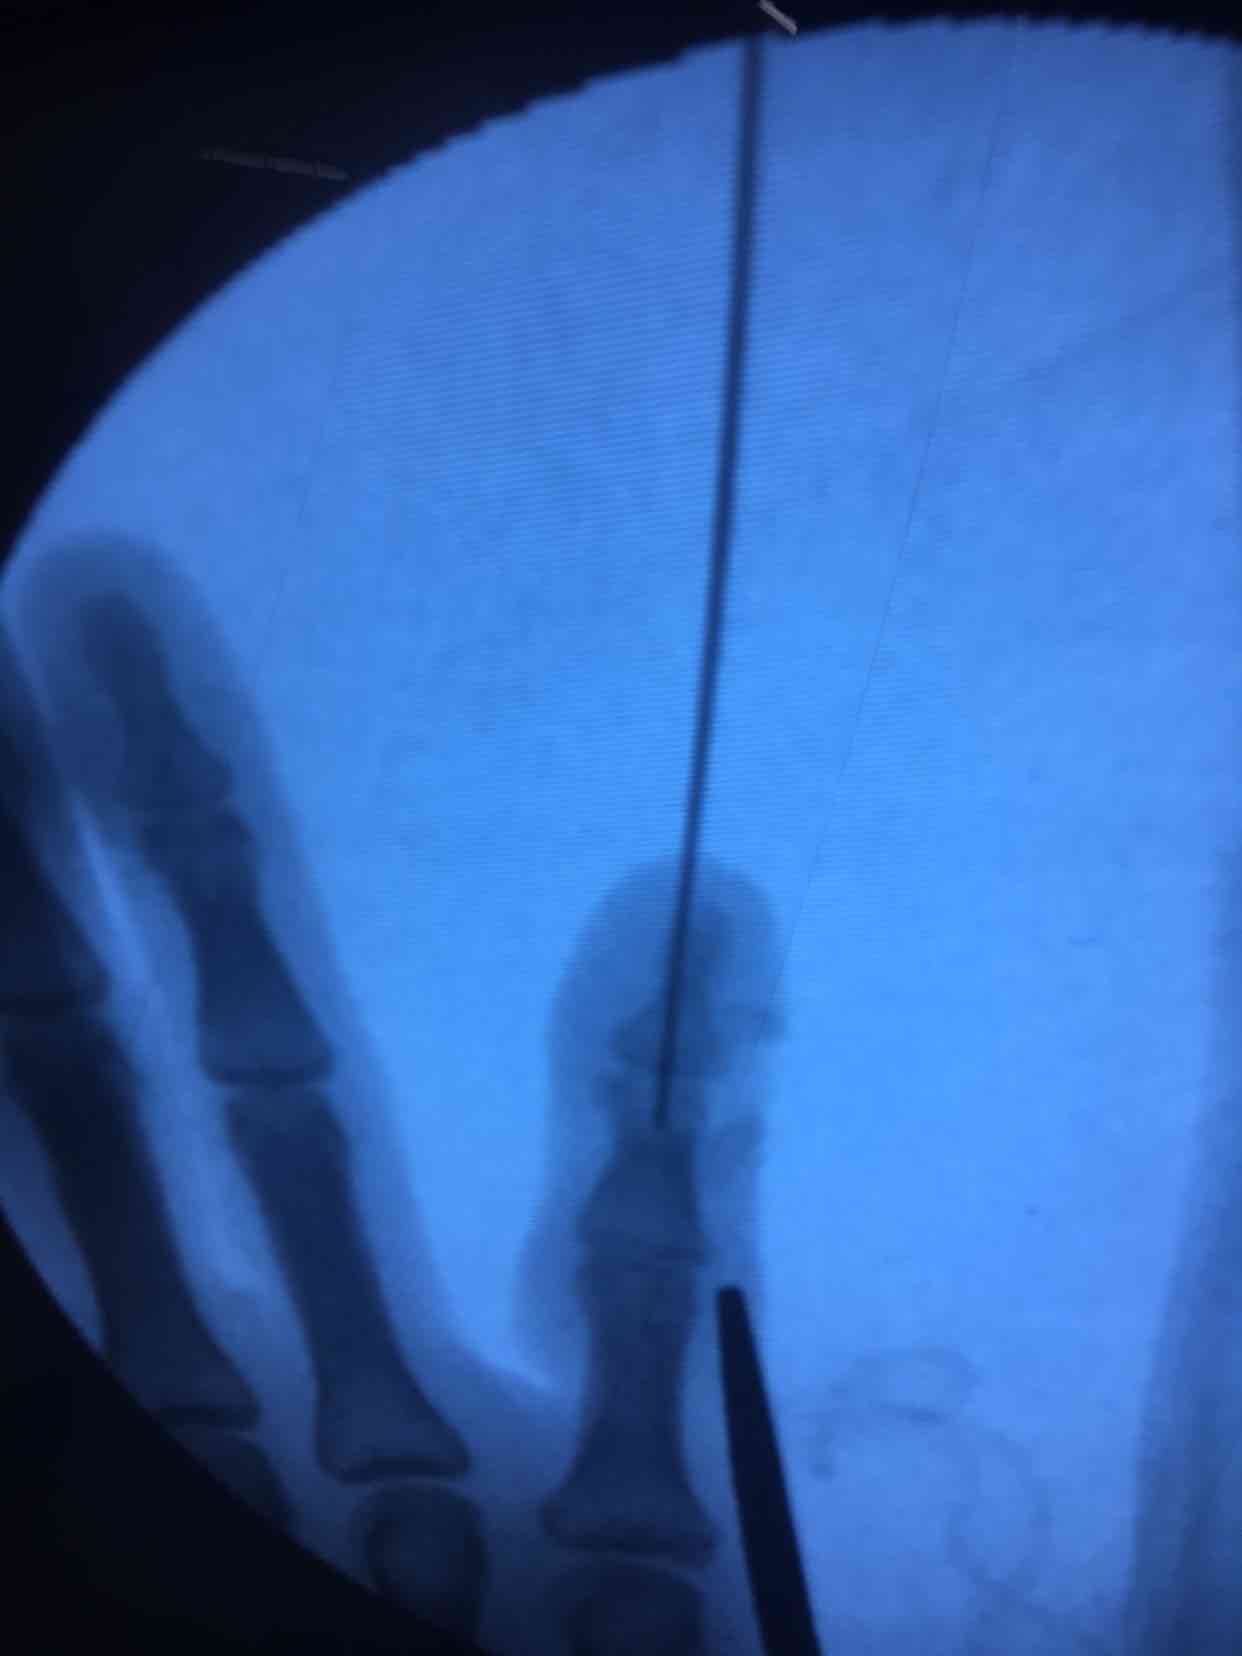

锤状指(切复内固定术)

完善术前准备,在指神经阻滞麻醉下行切复内固定术,术后制动4-6周,预防感染等处理。